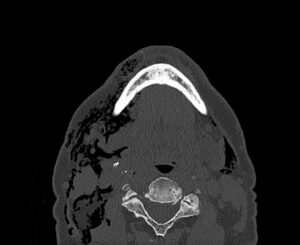

Dental Free Air CT Axial Unannotated. JETem 2025